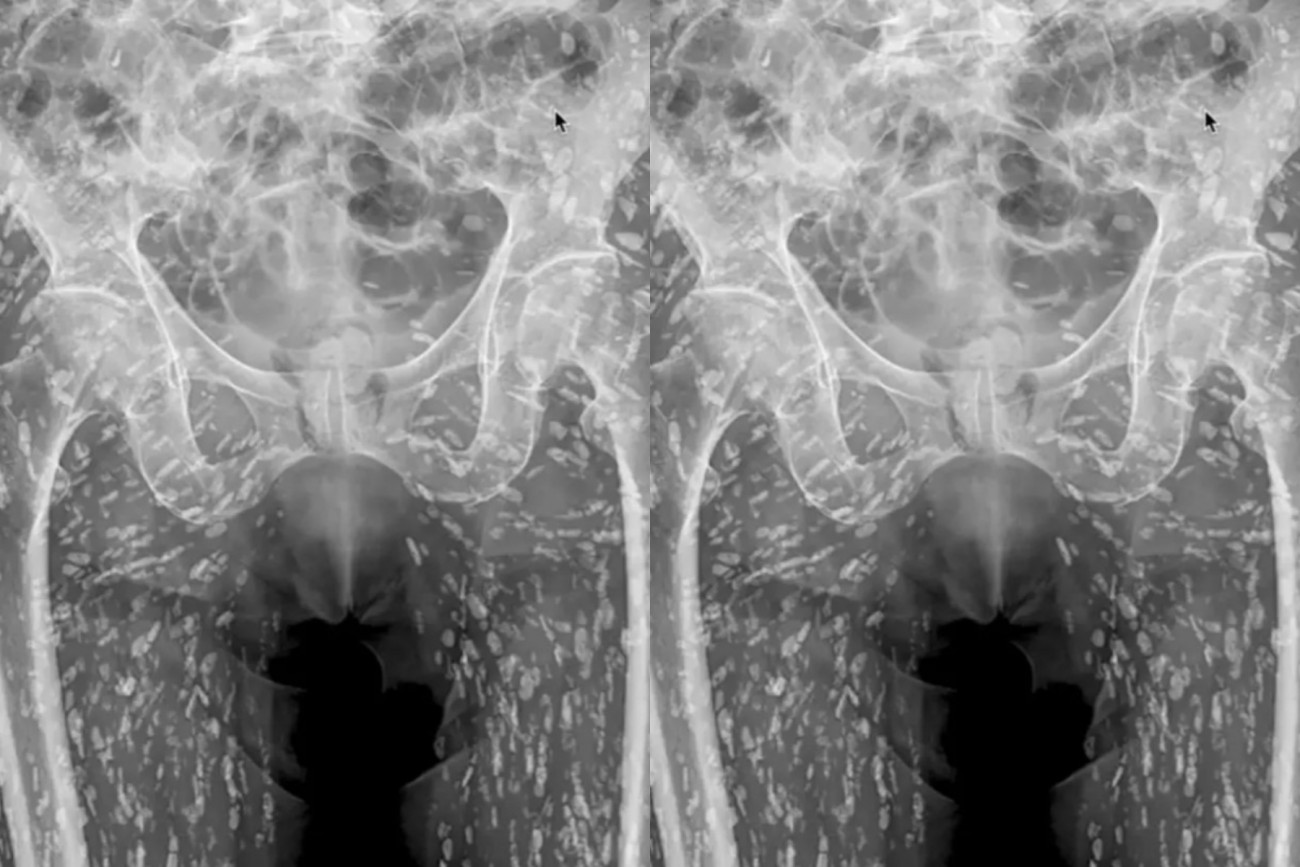

Ακτινογραφία αποκάλυψε ότι ένας άνδρας έχει μέσα του εκατοντάδες αυγά κεστώδη σκώληκα.

Ο αμερικάνος γιατρός Sam Ghali μοιράστηκε την ακτινογραφία του ασθενούς του στο X (πρώην Twitter) σχολιάζοντας πως είναι ««μία από τις πιο τρελές ακτινογραφίες που έχω δει ποτέ».

«Πρόκειται για μια πάθηση γνωστή ως κυστικέρκωση», πρόσθεσε ο ίδιος.

Σύμφωνα με τον Ghali, αυτό συμβαίνει όταν ο άνθρωπος καταναλώνει ωμό ή άψητο χοιρινό κρέας και στη συνέχεια μολύνεται με τα σκουλήκια στο γαστρεντερικό του σύστημα.

«Αυτές οι κύστεις μπορούν να ταξιδέψουν σε οποιοδήποτε μέρος του ανθρώπινου σώματος», εξήγησε ο Ghali.

«Σε αυτόν τον ασθενή έχουν μεταφερθεί σε μεγάλο βαθμό στους μυϊκούς και μαλακούς ιστούς των ισχίων και των ποδιών», συμπλήρωσε ο ίδιος.

Στη συγκεκριμένη περίπτωση, οι κύστεις δεν αποτελούν απειλή για τη ζωή του ασθενούς. Σε άλλες περιπτώσεις όμως μπορεί να οδηγήσουν ακόμη και στον θάνατο.

«Το πρόβλημα είναι ότι όταν αυτά ταξιδεύουν στον εγκέφαλο και κάθονται εκεί, μπορεί να προκαλέσουν πολύ σοβαρά προβλήματα», εξήγησε ο Ghali.

Τότε μιλάμε για νευροκυστικέρκωση που μπορεί να προκαλέσει πονοκεφάλους, επιληπτικές κρίσεις ακόμη και θάνατο.